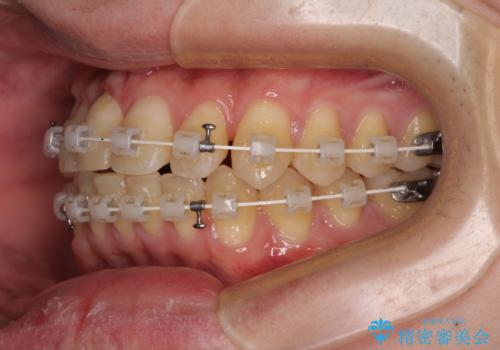

【モニター】前歯のデコボコとクロスバイト ワイヤー矯正で短期間に仕上げる

- 審美装置

- 前歯のデコボコとクロスバイトを気にして来院された患者様です。

インビザラインでもワイヤー装置でも矯正治療は可能でしたが、煩わしい自己管理なしに短期間で治療を行いたいとのことで、目立たないワイヤー装置にて治療を行うこととしました。